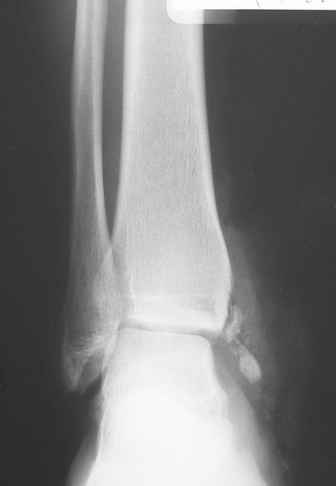

Уважаемые коллеги здравствуйте. Поступил пациент 27 лет травма

мотоциклетная Д/З:

Открытый перелом медиальной лодыжки с дефектом костной ткани, обширная

рвано-скальпированная рана передне-медиальной поверхности г/стопного

сустава с

дефектом мягких тканей. При поступлении ПХО пластика дефекта кожи

перемещенным лоскутом. В послеоперационном периоде ввиду синюшности

перемещенного лоскута швы сняты.По формировании зоны некроза -

некрэктомия, дерматомная аутопластика. Пластика состоятельная. Какие

будут соображения по дальнейшей такике? На сколько пациент может

реабилитироваться в плане функции г/стопного сустава?